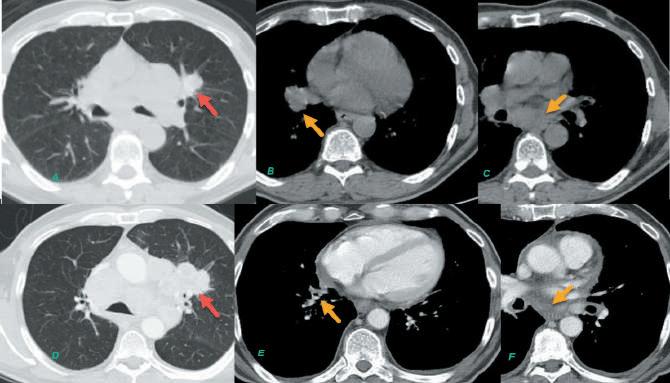

Practical Example — Potential Differences in NSCLC Read Outcomes “Axial CT chest images of a subject enrolled in non-small cell lung cancer trial, baseline images (top row) and follow-up images (bottom row). (A) Baseline CT image in lung window shows a left upper lobe lung mass (red arrow) selected as target disease; two mediastinal nodes (yellow arrows) seen on soft tissue window (B, C) were selected as non-target disease by the site reviewer due to lack of intravenous contrast. On the follow-up, (D) CT image in lung windows shows the target lung mass increased significantly resulting in progressive disease by target disease, even though the nontarget mediastinal nodes had decreased in size as seen on the soft tissue window (E, F). For the central review, due to strict guidelines and ongoing reminders for measuring as many lesions as possible, the central reviewer measured lung mass and mediastinal nodes as target disease at baseline, to include maximum target lesions possible. Hence despite the increase in size of lung disease, because the mediastinal nodes had decreased in size significantly, overall assessment was partial response on follow-up.” - Dr. Nisha Sainani

Figure 1: Follow up CT chest in a patient enrolled in advanced prostate cancer trial with evidence of new mediastinal node? Metastasis? Secondary Malignancy. Biopsy needed for confirmation.